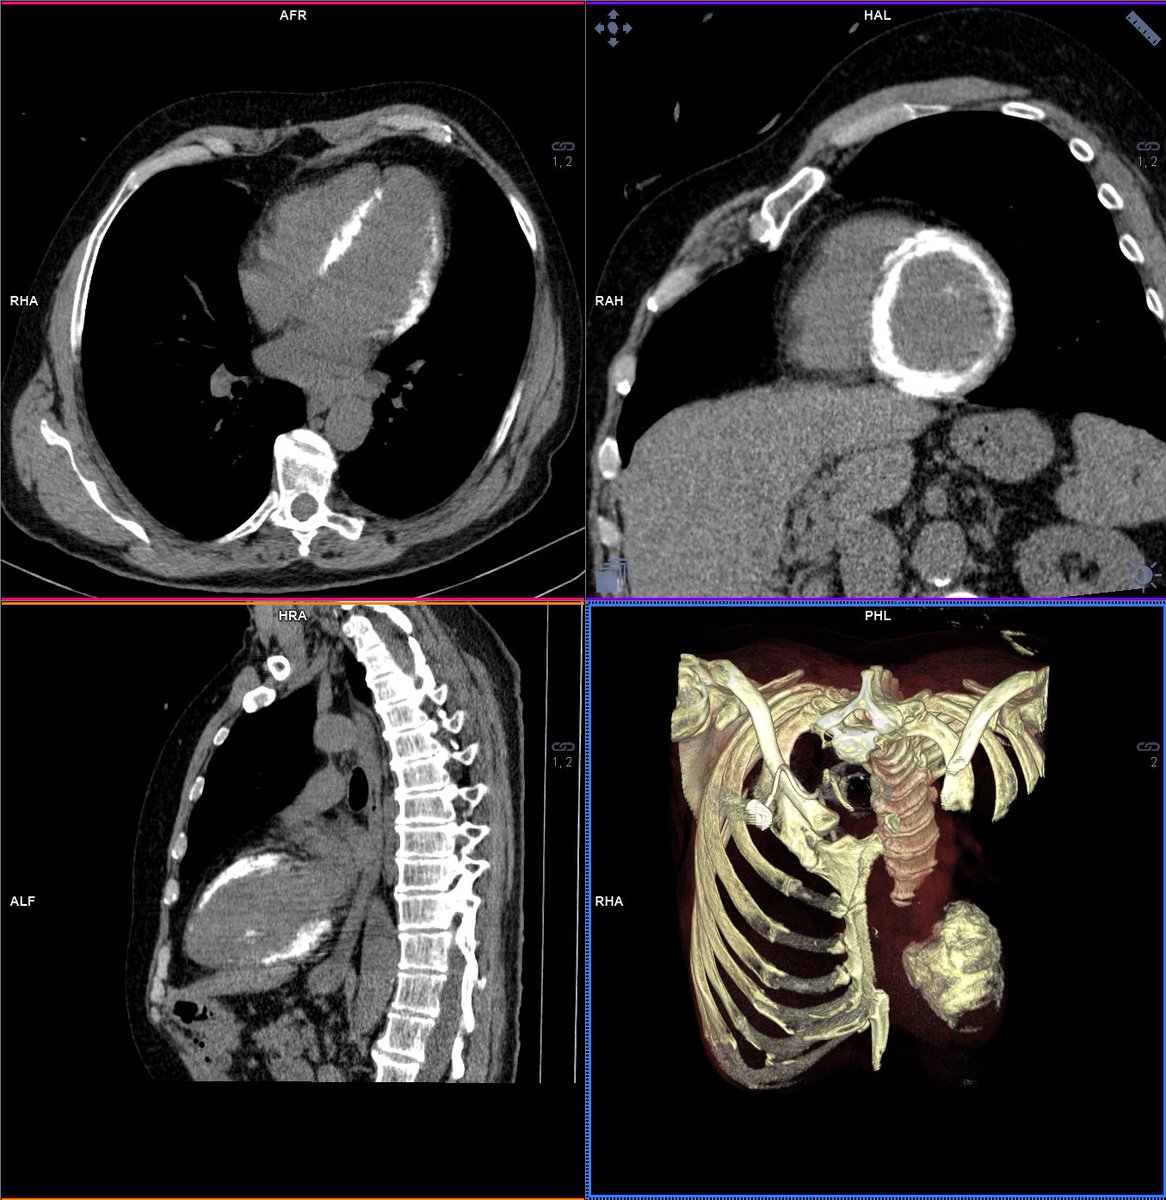

Skip the non-contrast CT in #YesCCT aortic valve assessment? CCT indexed aortic valve calcium volume accurately Dx severe AS & predicts valve replacement or death w/out separate non-contrast CT in multicenter registry study jacc.org/doi/10.1016/j.… #JACCIMG #cvImaging #vhdAS